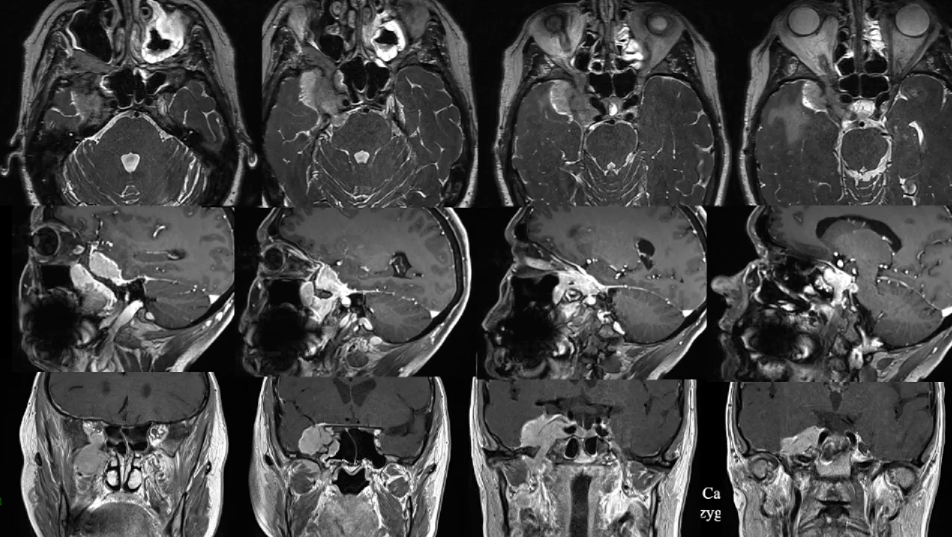

这个凶险的颅底脑膜瘤在短短半年间显露出惊人的侵略性——它从海绵窦这个“危险三角区”发难,不仅快速向颞窝扩张领地,更是一举攻陷了蝶腭窝和蝶窦这两大要塞。肿瘤如此迅猛的进展态势,必须立即手术解除危机!

手术前影像